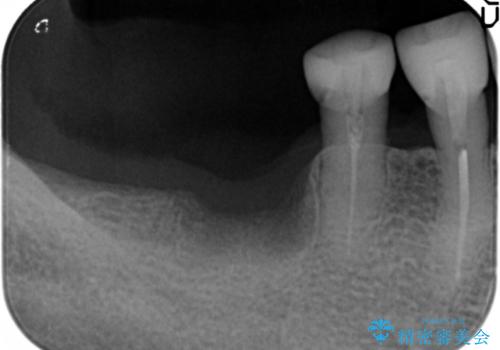

- 奥歯の違和感を主訴に来院された患者様です。

精査したところ、右下の奥歯は大きなう蝕により保存不可能な状態でした。

患者様のご希望により、抜歯後インプラント治療を行いました。